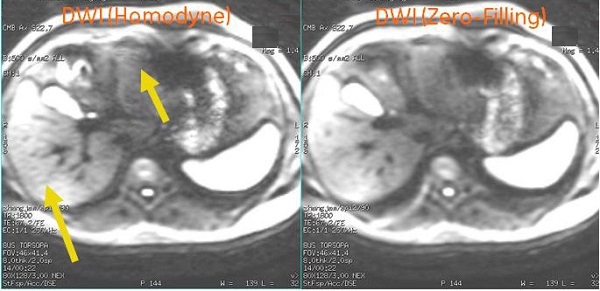

The User CV Recon Type is only available with DWI scans. It is typically used with liver scans. There are two Recon Type states:

- Set Recon Type = 0 and a zero-filled reconstruction technique is used. It significantly reduces streak (worm-hole) artifacts particularly in images with low SNR and motion. The trade-off for reduced artifact is slightly lower resolution or blurred images in comparison with Homodyne reconstruction.

- Set Recon Type = 1, the default, and a homodyne reconstruction technique is used. This option produces a sharper image but is more susceptible to worm-hole artifact.